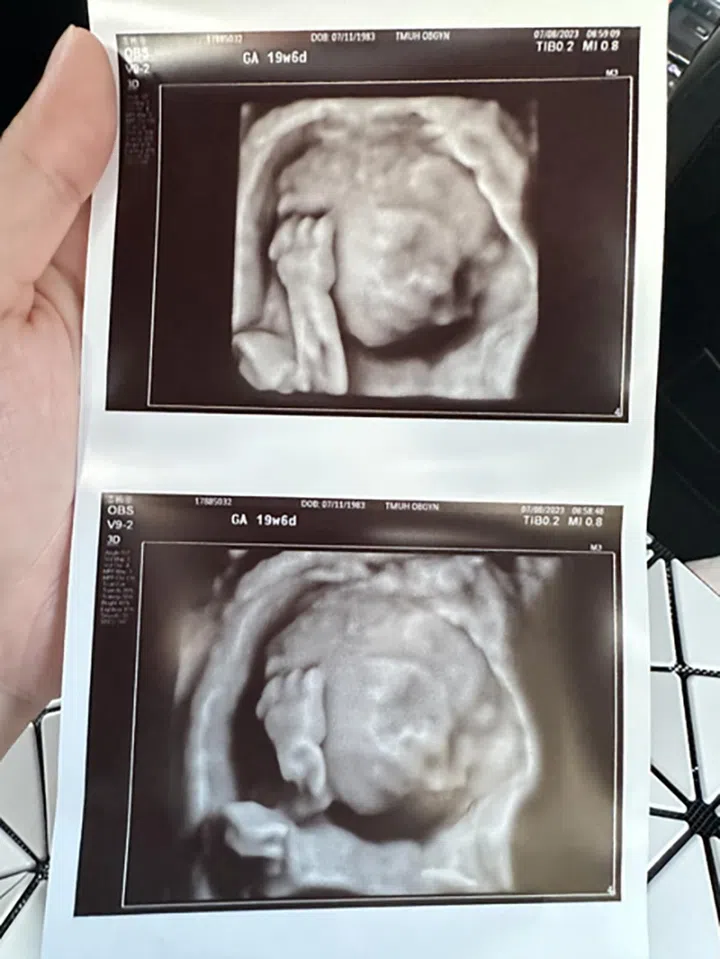

潘嘉丽分享如“过山车”的孕期

恭喜潘嘉丽即将当妈妈,可是她坦言40岁高龄怀第一胎,她一路走来不简单。

我的1st trimester挺糟糕的,原以为至多会孕吐或胃口不好,结果不只孕吐超多、偏头疼到睡不着,还胃疼到哭,并出现严重胃胀风,明明还没3个月,肚子却看起来像4个月!那时候Roger每晚都要帮我拍嗝,因为真的太难受,我甚至一度不能走路,要买拐杖。可能因为我扩张的骨盆按压到神经,结果一直抽筋而影响到步行。我怀孕的前三个月也一直出血,必须吃药,还要卧床休息。我就是那种害喜check all the list的孕妇 。

在经历这一切,我也一直告诉自己要保持平常心。所以一直没有公开怀孕的消息,等到该做的测试都pass了,才跟大家分享。